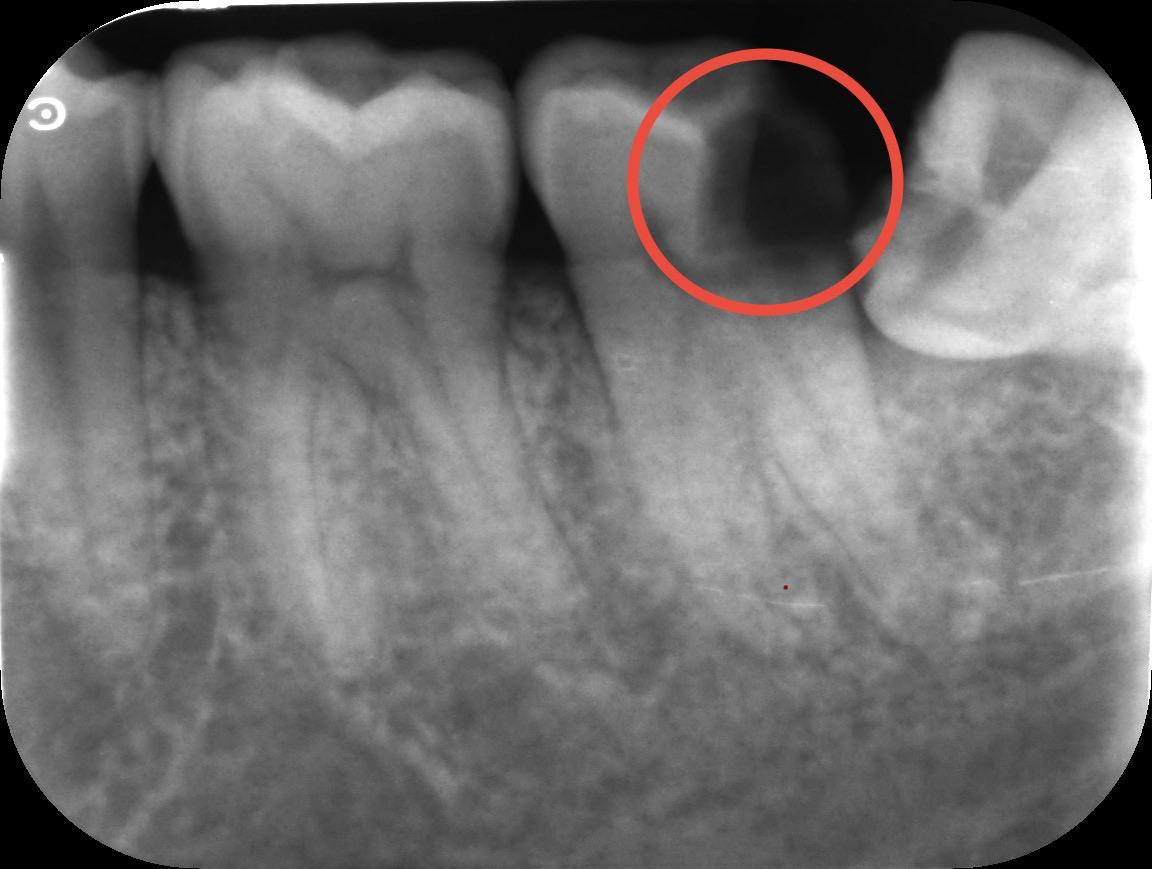

Conduct a thorough examination, including X-rays, to determine the extent of the infection. Discuss the treatment plan and address any concerns. In complex cases, the patient may be referred to an endodontist, a specialist in root canal procedures.